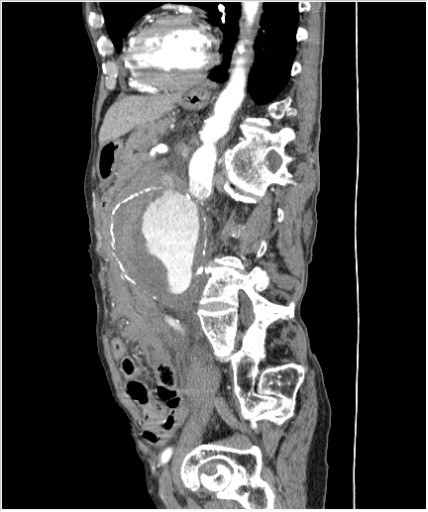

КТ брюшной полости. Мужчина с пальпируемой опухолью в животе

Пациент Т. 64 года, обратился на КТ брюшной полости амбулаторно (!), по направлению семейного врача с диагнозом abdominal mass, буквально: образование брюшной полости.